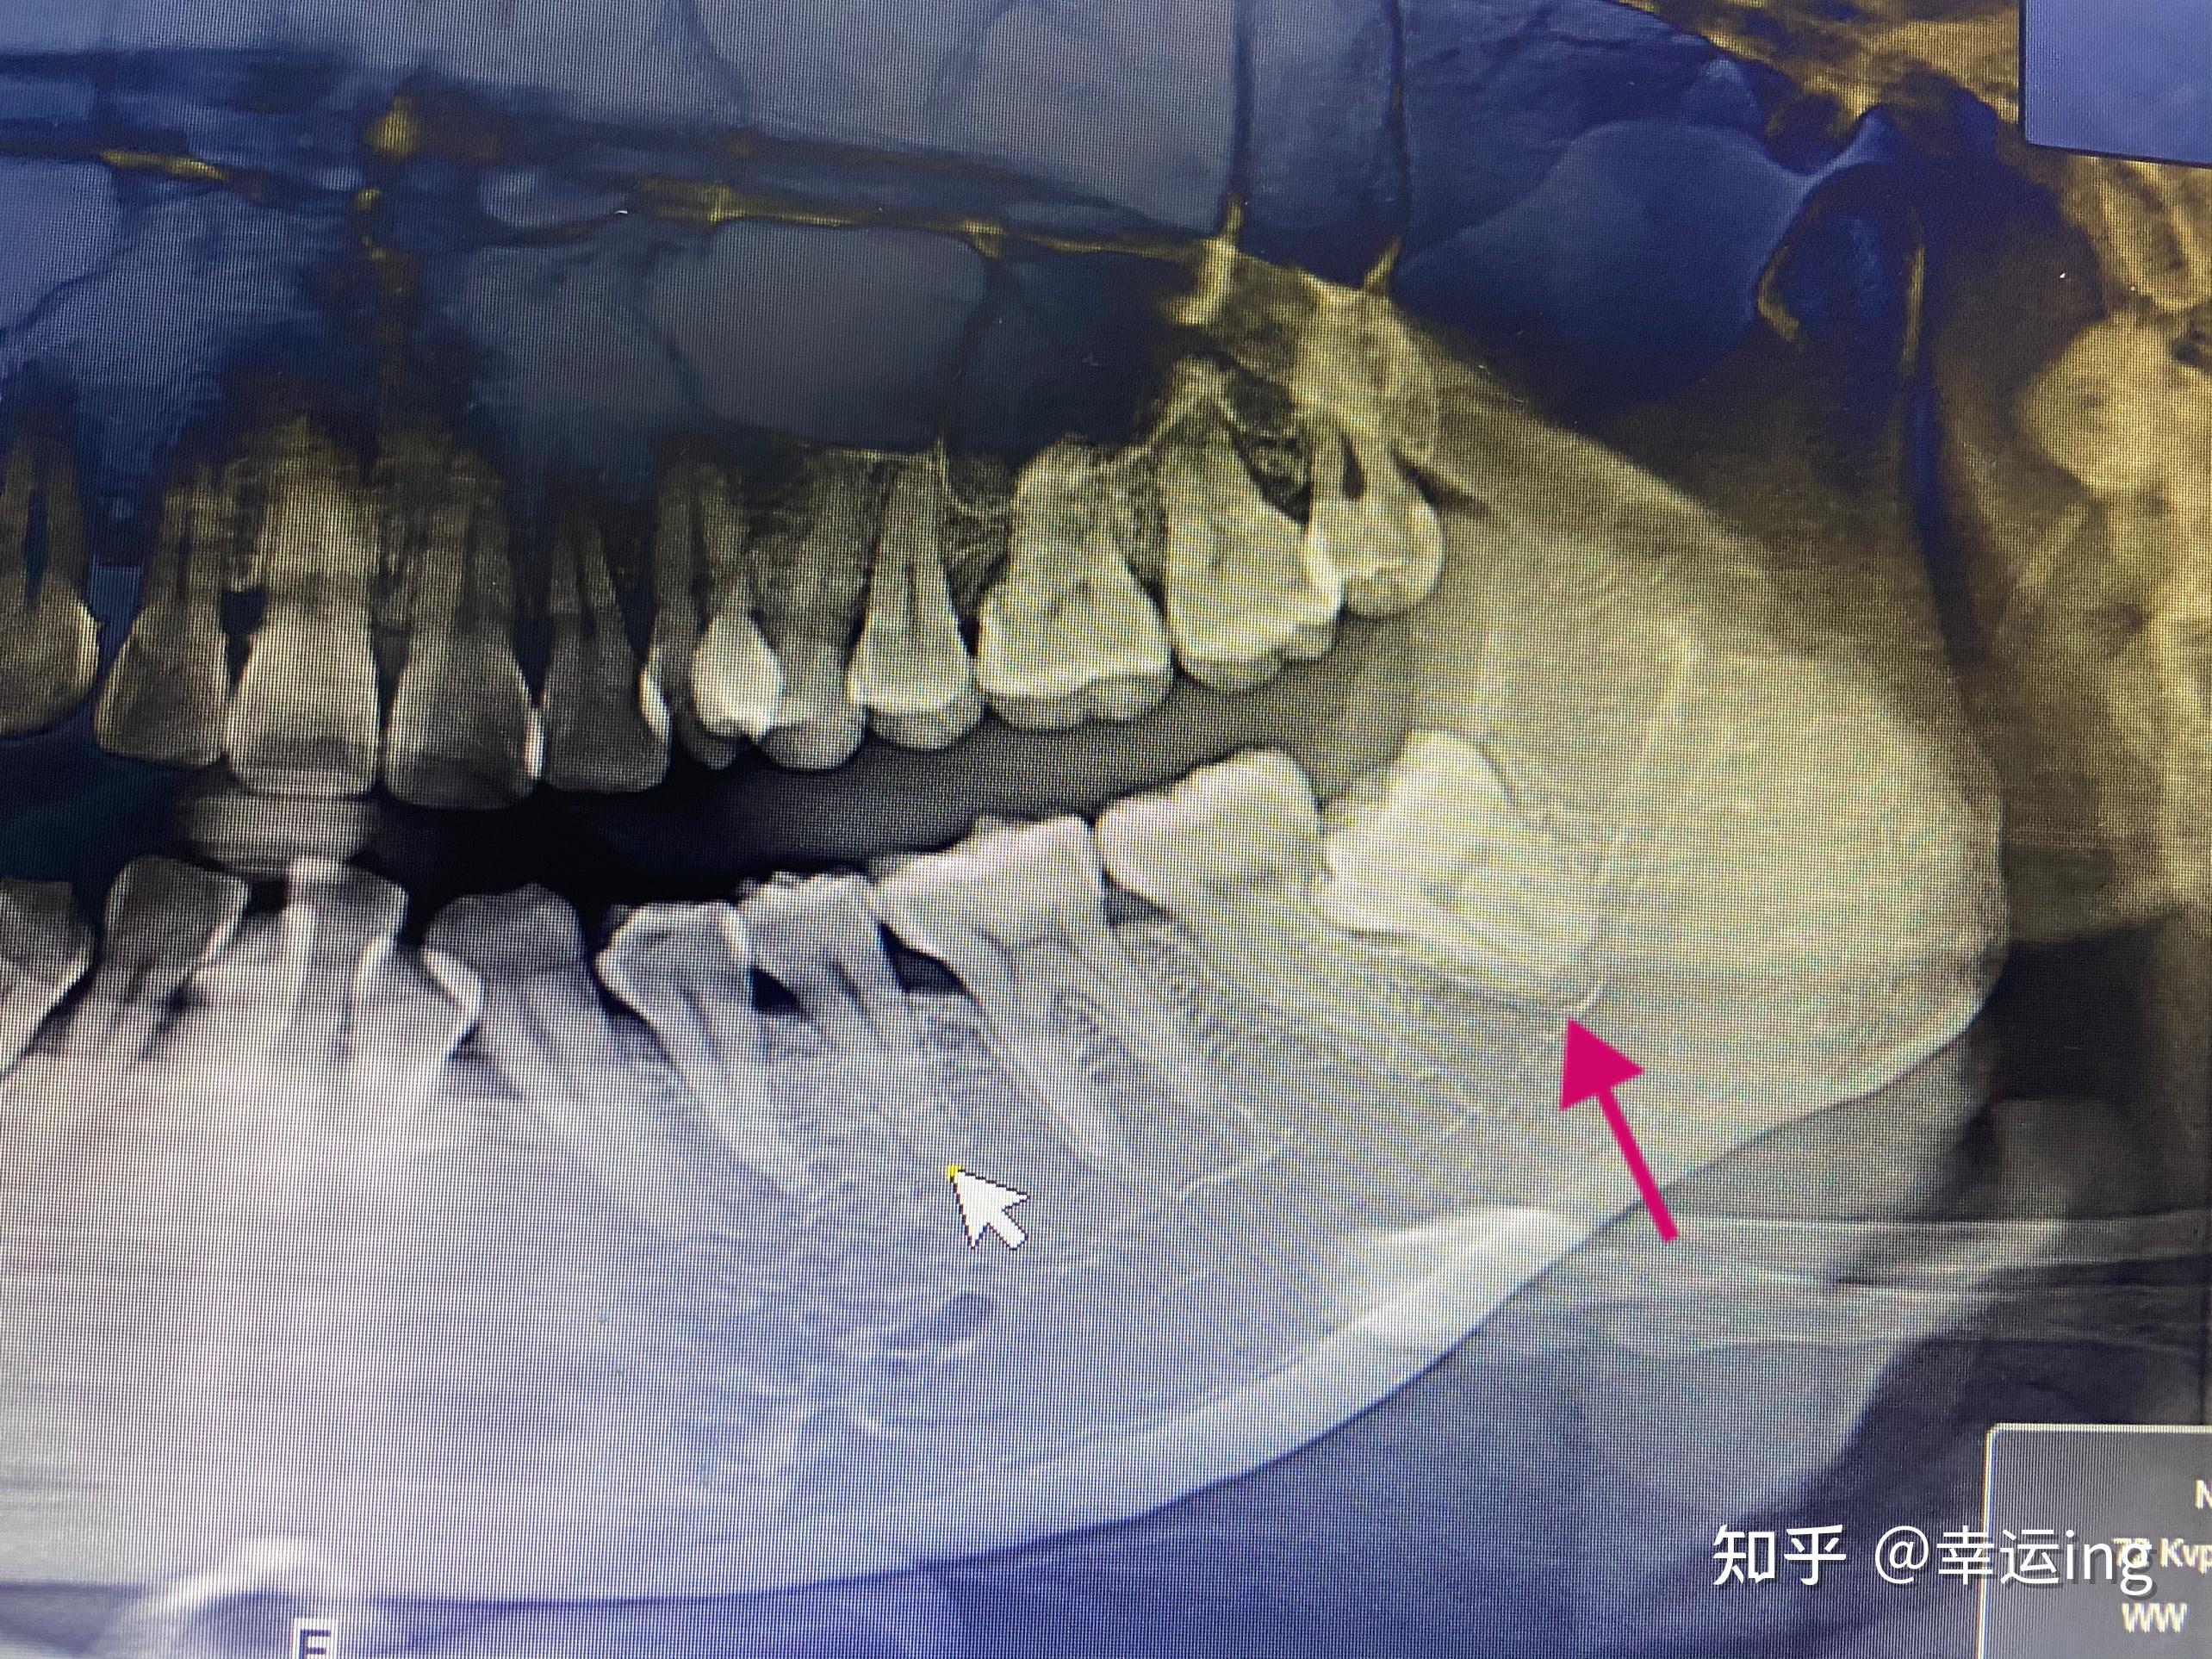

疑似串通神经管的智齿